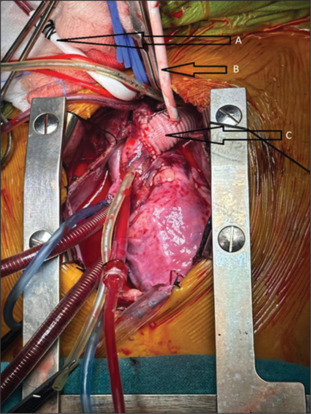

We present a case of a 4-year-old boy with posttraumatic non-A non-B aortic dissection. Pediatric aortic dissection is a rare entity with ill-defined risk factors. A high index of suspicion is needed to identify these patients with aggressive management to offset a high mortality rate. Diagnosis was established with a computed tomography scan, which showed a dissection flap in the aortic arch. The child was taken up for surgery and underwent successful aortic arch replacement with arch vessel reimplantation. We report this case not only because of its incidental rarity but also to highlight the meticulous planning and execution that was essential for a successful outcome.